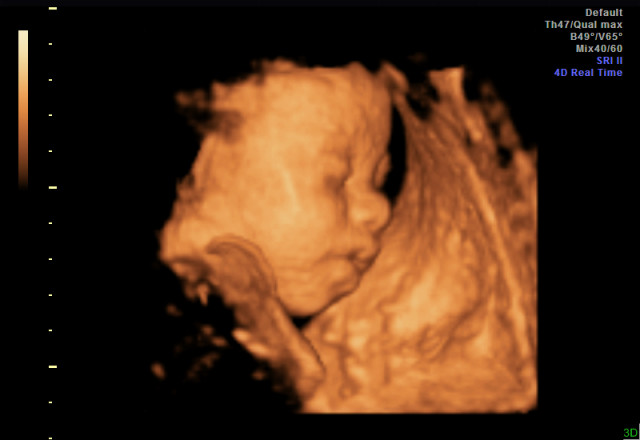

Yesterday I had a 3d ultrasound and it was an amazing experience! Before having it done, I wasn't sure if it was worth the money, but after, I can say that it is for sure worth every penny! The ultrasounds I've had at the doctor's office have been very short, rushed, and not detailed at all. With the 3d ultrasound, we got to see every part of the baby and in great detail. She even yawned and hiccupped while we were watching, which was adorable! If anyone is considering it and on the fence, you should do it and you will be so happy you did.

That's amazing. Such a gorgeous baby. I am now considering doing it.